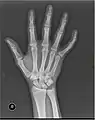

Fracture

The neck of a metacarpal is a common location for a boxer's fracture, but all parts of the metacarpal bone (including head, body and base) are susceptible to fracture. During their lifetime, 2.5% of individuals will experience at least one metacarpal fracture. Bennett's fracture (base of the thumb) is the most common.[4] Several types of treatment exist ranging from non-operative techniques, with or without immobilization, to operative techniques using closed or open reduction and internal fixation (ORIF). Generally, most fractures showing little or no displacement can be treated successfully without surgery.[5] Intraarticular fracture-dislocations of the metacarpal head or base may require surgical fixation, as fragment displacement affecting the joint surface is rarely tolerated well.[5]

Multiple fractures of the metacarpals (aka broken hand). (Right hand shown with thumb on left.)